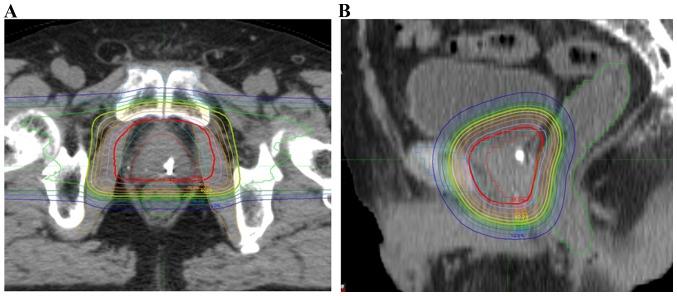

The efficacy and safety of proton beam therapy (PBT) were retrospectively evaluated in 111 consecutive patients with prostate cancer who underwent definitive PBT between 2008 and 2012. Following exclusion of 18 patients due to treatment suspension, loss to follow-up, and histology, the analysis included 93 patients with a median age of 68 years (range, 49-81 years). A total of 7, 32 and 54 prostate cancer patients were classified as low-, intermediate- and high-risk, respectively, as follows: High-risk, T≥3a or prostate-specific antigen (PSA) ≥20 ng/ml or Gleason Score ≥8; low-risk, T ≤2b and PSA≤10 ng/ml and Gleason Score=6; intermediate-risk, all other combinations. The median initial prostate-specific antigen (PSA) level was 9.75 ng/ml (range, 1.4-100 ng/ml) and the median Gleason score was 7 (range, 6-10). Patients with low-risk disease received 74 GyE (relative biological effectiveness=1.1) in 37 fractions, and those at intermediate or higher risk received 78 GyE in 39 fractions. Complete androgen blockade (CAB) therapy was performed from 6 months prior to PBT for patients with intermediate- or high-risk disease. CAB was continued during PBT and then terminated at the end of PBT for intermediate-risk patients. Patients at high risk continued CAB for 3 years. No combination therapy was used for low-risk patients. All the patients were followed up for >2 years after PBT, and all but one were PSA failure-free. The Common Terminology Criteria for Adverse Events v.4.0 was used to evaluate late adverse events. One patient developed grade 3 non-infectious cystitis and hematuria. Grade 2 urinary frequency was observed in 1 patient, and grade 2 rectal bleeding occurred in 4 patients. Of the 4 patients with grade 2 rectal bleeding, 2 received anticoagulant therapy, but none had diabetes mellitus or another high-risk comorbidity. The median time to occurrence of an adverse event of grade ≥2 was 14 months (range, 3-41 months). Therefore, the present retrospective study revealed that PBT at 78 GyE/39 Fr was well-tolerated and achieved good tumor control in patients with prostate cancer.